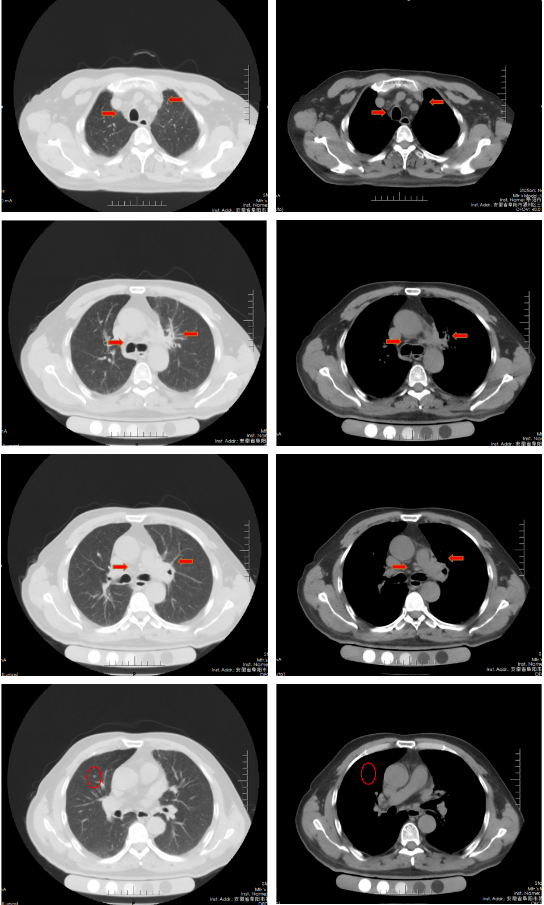

胸部增强CT(2022-02-12):左肺门及纵隔内见团块状软组织密度影,大小约62mm×42mm,边界不规整,内见血管影穿行,增强扫描呈轻度强化,局部支气管狭窄,远端肺内见片状磨玻璃密度影,边界欠清。右肺上叶见结节状密度增高影,较大直径约为8mm,增强扫描呈轻中度强化,右侧斜裂见长径约为6mm的高密度影,增强扫描未见明显强化;两肺透亮度增强,左肺下叶胸膜下囊状透光区。余气管、支气管通畅,未见明显狭窄、阻塞。纵隔和左肺门区见多发肿大淋巴结影,部分融合。两侧胸腔无明显积液。胸部CT诊断:左肺门及纵隔内占位,考虑肺Ca;纵隔及左肺门淋巴结肿大;右肺上叶结节,转移可能;右侧斜裂下结节;两肺肺气肿、左肺下叶肺大泡。

胸部CT(2022-04-12):左肺门及纵隔内见团块状软组织密度影,大小约57mm×37mm,边界不规整,局部支气管狭窄,远端肺内见片状磨玻璃密度影,边界欠清。右肺上叶见结节状密度增高影,较大直径约为9mm,右侧斜裂见长径约为7mm的高密度影;两肺透亮度增强,左肺下叶胸膜下囊状透光区;两肺可见索条状影。余气管、支气管通畅,未见明显狭窄、阻塞。纵隔和左肺门区见多发肿大淋巴结影,部分融合。两侧胸腔无明显积液。胸部CT诊断:左肺占位复查;纵隔及左肺门淋巴结肿大;右肺上叶结节,转移可能;右侧斜裂下结节;两肺肺气肿、左肺下叶肺大泡。

治疗后评价:经过EP方案治疗后两周期,患者仍有咳嗽、咳痰及左侧胸痛,症状无缓解,且出现体重下降;影像学检查提示左肺病灶及纵膈淋巴结及肺门淋巴结较前缩小不明显(缩小<30%),疗效评价SD。总体效果欠佳。